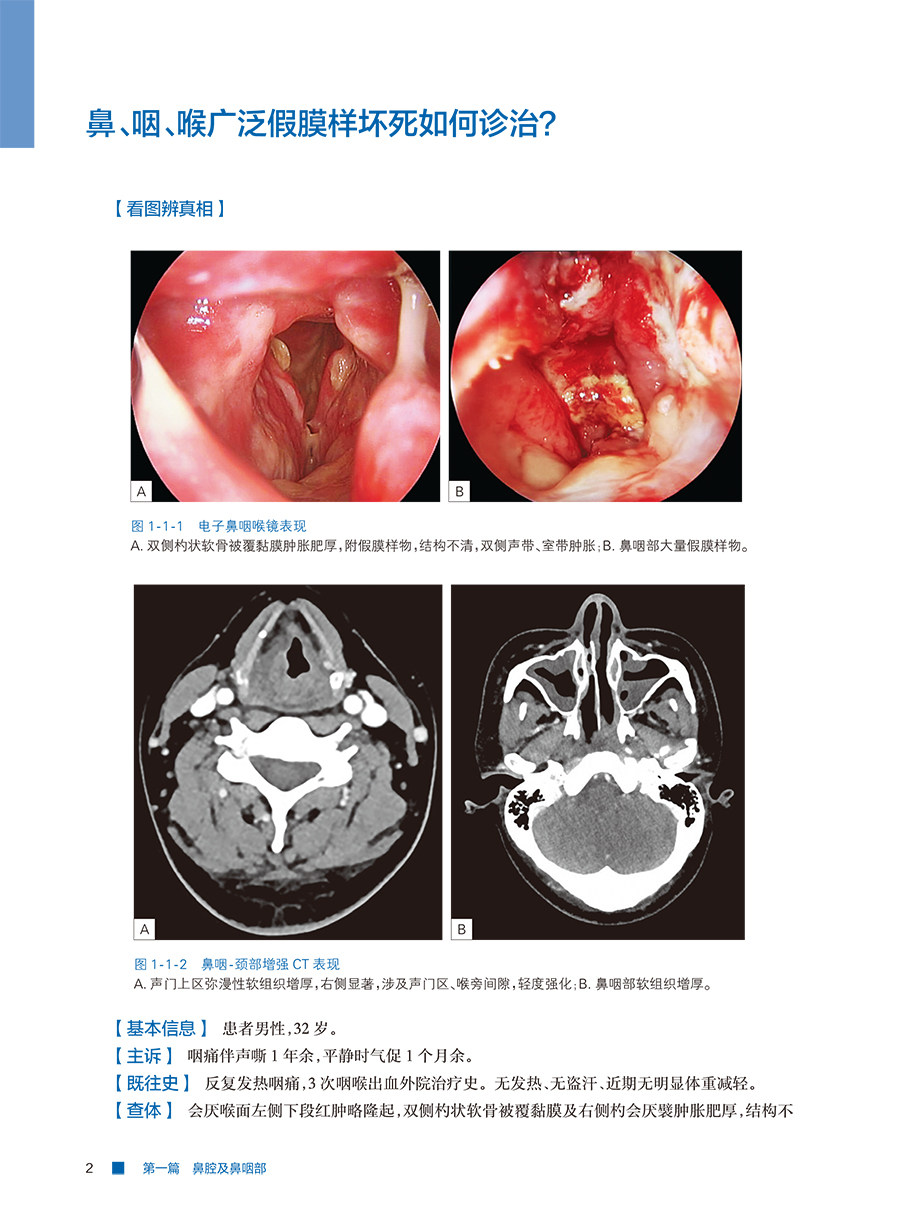

本书精选近3年来颇具讨论价值的20例疑难病例,其均来自复旦大学附属眼耳鼻喉医院头颈外科中心及国内优势头颈外科中心。每一病例按病史简介、思考、病例解析、讨论四个环节编写。编写从患者简要病史出发,引发诊疗难点的3个核心思考问题,病例解析环节围绕3个问题对诊断难点、治疗难点、治疗经过、最后诊断、随访及转归进行介绍,讨论环节结合关键检查结果,进行了详尽的病因回顾、临床表现回顾、术前评估手段回顾、治疗策略回顾。本书旨在通过环环相扣的病例解析,帮助读者以书中病例为依据举一反三地解决临床中的类似问题。